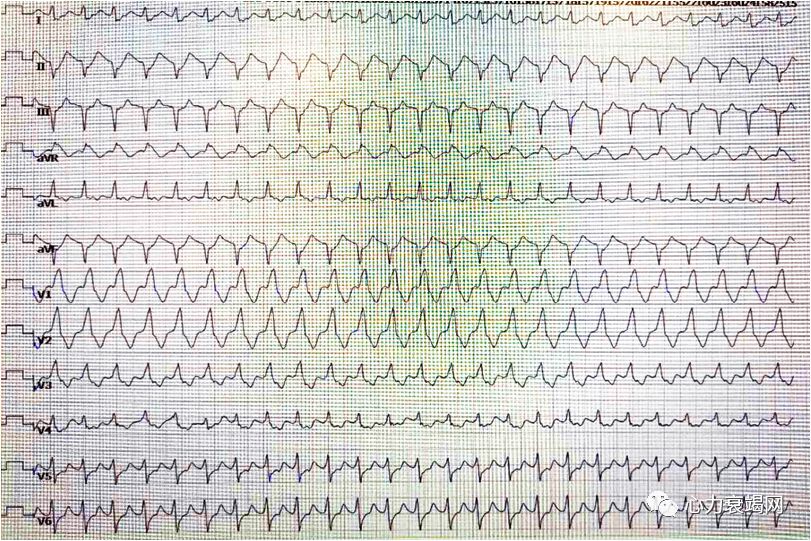

心电图

1)入EICU时患者气管插管、镇静状态,心电图提示心房颤动;

室性心动过速